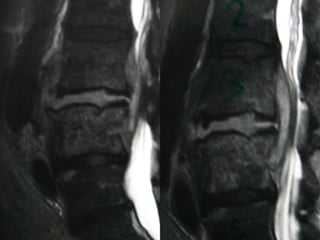

Magnetic resonance imaging

lumbosacral spine showing a

T1W isointense lesion

intradural extramedullary

lesion at D12-L1 level

measuring about 11.4 × 11.2

× 22.8 mm displacing the

conus and cauda (a and b).

On contrast (c and d) there is

heterogenous enhancement

with hypointense center and

peripheral enhancement